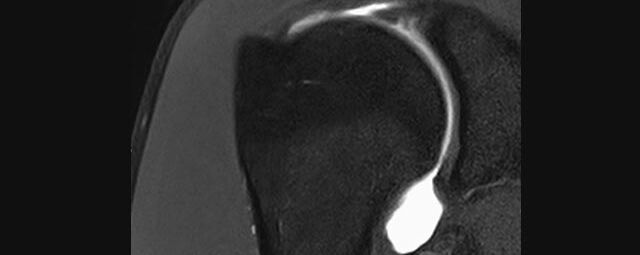

Gelenke

• Beurteilung von Knochen, Bändern und anderen Weichteilstrukturen der Gelenke nach Unfall.

• Arthrosediagnostik (Knorpelschaden)

• Impingement-Symptomatik

Arthrographie

• MR-Arthrographie – nach örtlicher Betäubung und gründlicher Desinfektion der Haut wird unter Lagekontrolle mit Röntgen-Durchleuchtung eine kleine Nadel in den Gelenkraum positoniert und darüber ein MR-taugliches Kontrastmittel in den Gelenkraum gespritzt. Danach wird die Nadel entfernt. Anschließend erfolgt die MRT des Gelenkes. Diese Methode stellt kleine anatomische Strukturen des Gelenkraumes verbessert dar, z.B. zur Therapieplanung vor Arthroskopie bei Sportverletzungen der Schulter oder Gelenkinstabilität.